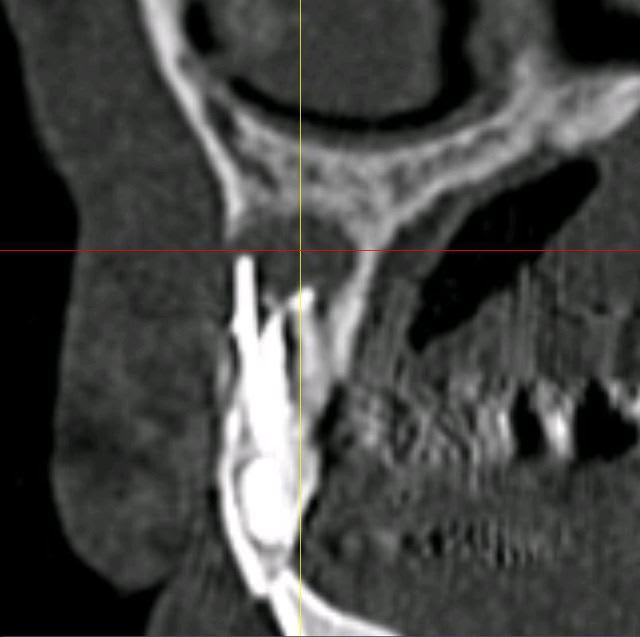

Mon petit cas galère du moment...

Péri-implantite 14 et 26.

25 explosée.

Infection apicale 13, 12, 33 (chaque 2 mois sous antibio depuis pas mal de temps...)

Et gros bouchon de fugy de 2 à 3 mm au fond du logement de l'inlay core, que j'ai dû traverser à la fraise diamantée pour pouvoir retraiter la 13 et la 12... :-)